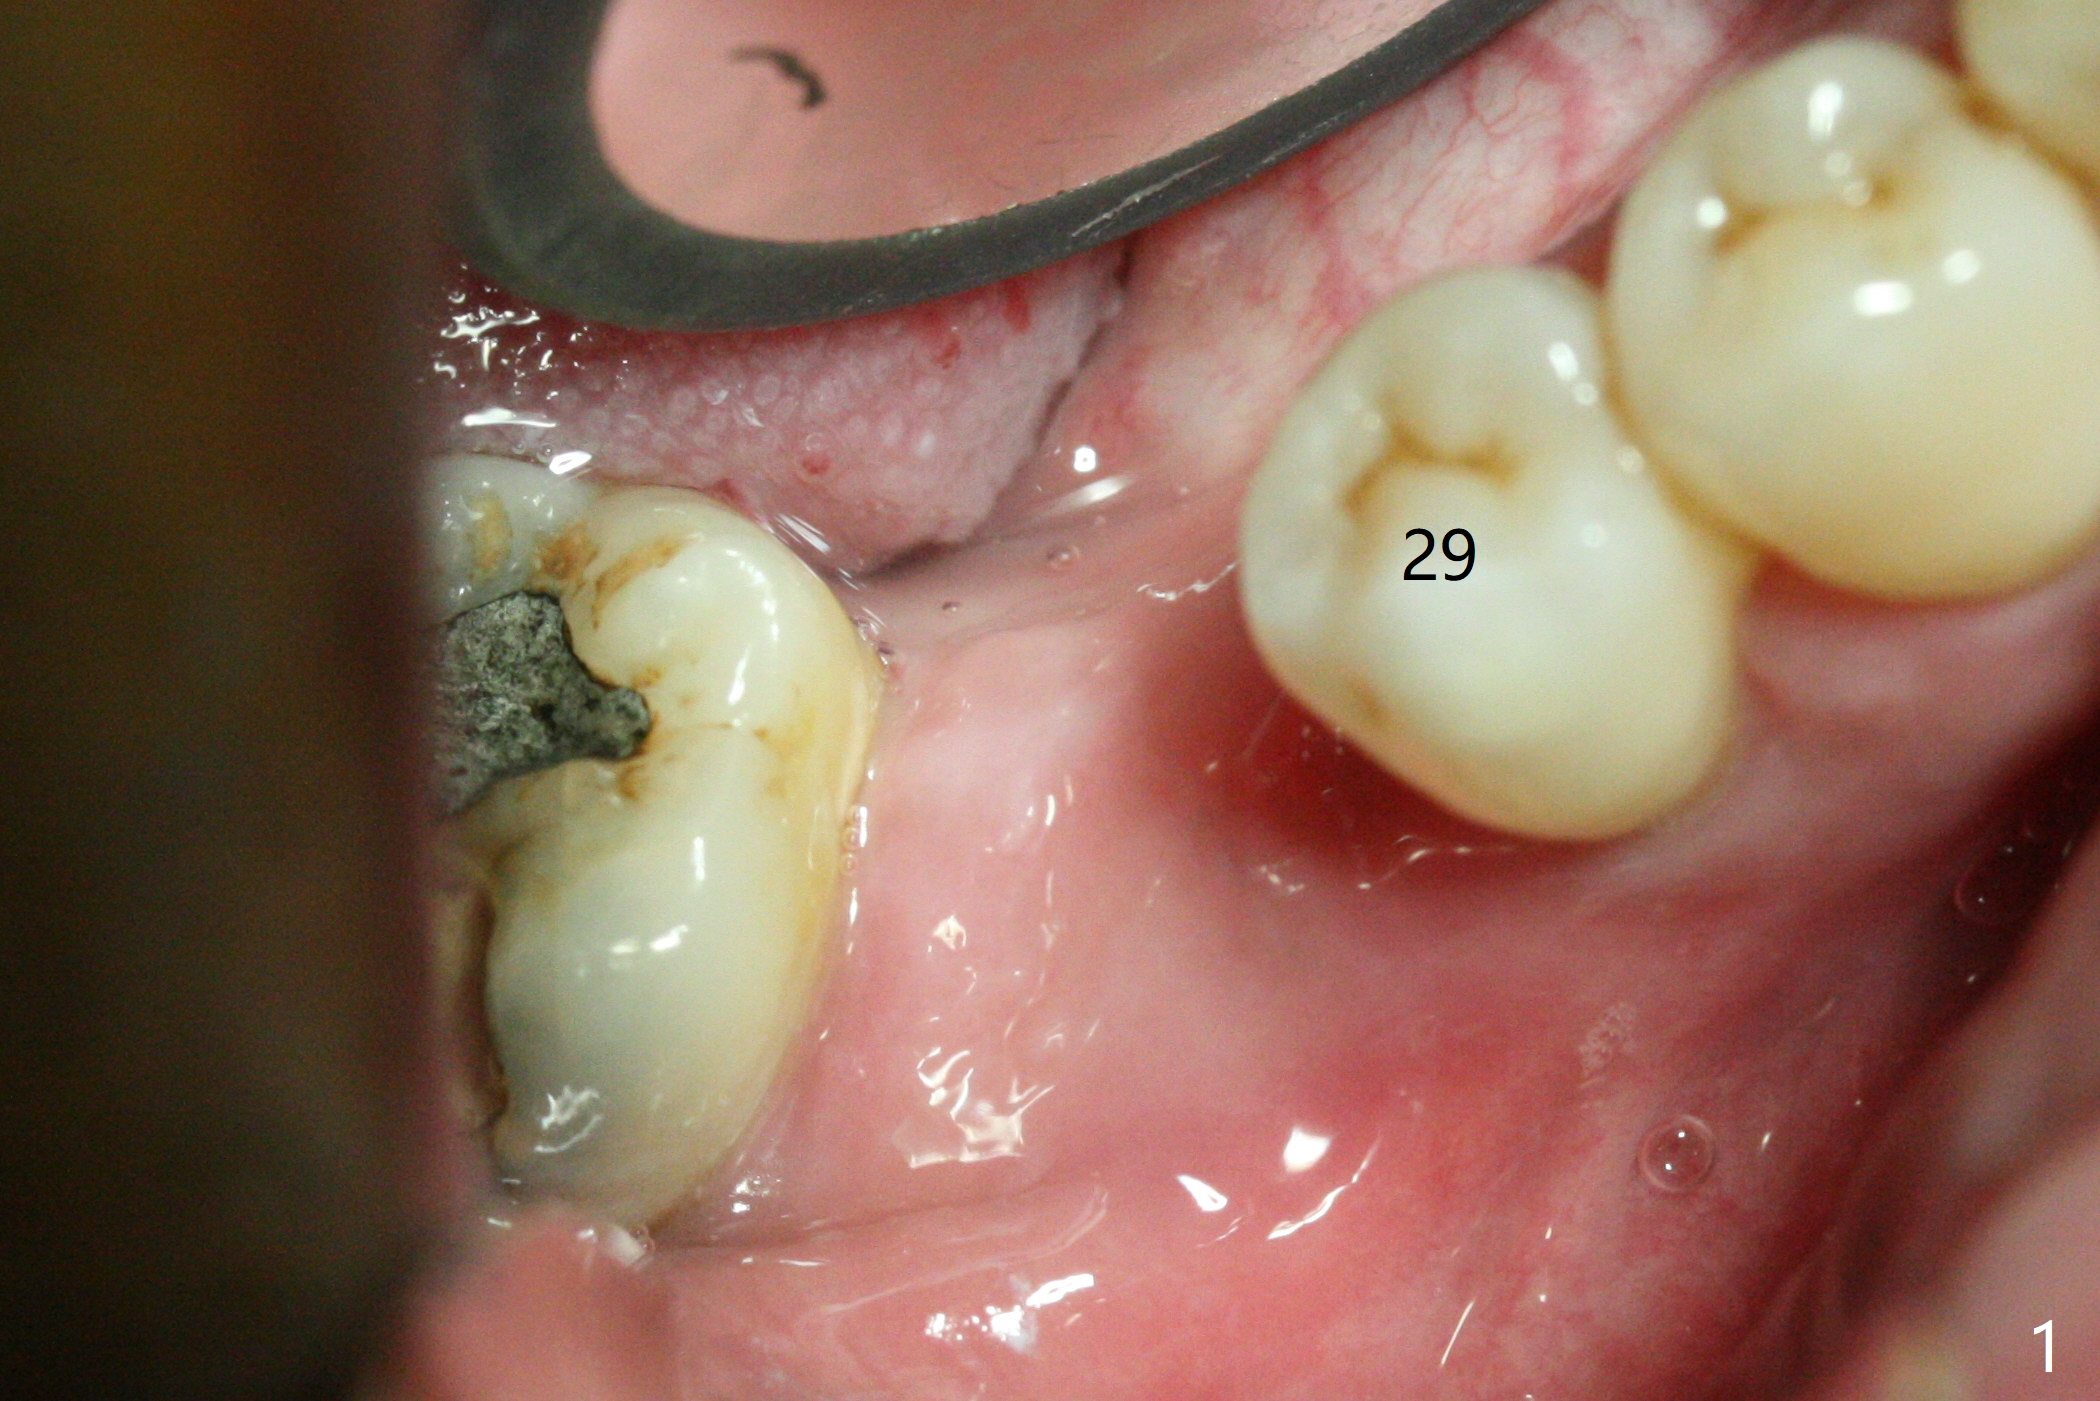

The ridge at #30 is not so narrow (Fig.1). Initial depth is 10 mm with 2 mm from the Inferior Alveolar Canal (Fig.2,3 red dashed line). A 4.5x10 mm implant is placed with > 50 Ncm; a 6.2x5(3) mm healing abutment placed (Fig.4). The implant is stable and seems to be ready for impression 3 months postop (Fig.5). CT taken 5 months post cementation shows that the implant could be placed more lingually (Fig.6 (coronal section; B: buccal)). Periradicular radiolucency at #31 (Fig.7 *) is continuous with the Inferior Alveolar neurovascular bundle (N). After extraction, care should be taken to remove granulation tissue. The tooth #32 will be extracted simultaneously because of severe bone loss.